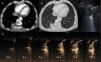

A y B) TC de tórax tras la administración de contraste yodado intravenoso en ventanas mediastino (A) y de pulmón (B) en el que se visualiza nódulo sólido subpleural (flecha blanca) con engrosamiento pleural adyacente (flecha negra) e incurvación broncovascular (flecha gris). C) Ecografía torácica en modo B: consolidación redondeada (flecha blanca) asociada a un engrosamiento pleural focal (flecha negra). D) Serie de imágenes de la ecografía torácica con contraste (aparece en cada imagen el tiempo transcurrido desde la administración del mismo) en el que se pone de manifiesto una rápida captación del mismo, antes de los 6s, que inmediatamente se convierte en homogénea y no muestra lavado tras más de un minuto de exploración.

A pesar de que los hallazgos radiológicos orientaban hacia una atelectasia redonda, la dudosa presencia de crecimiento de lesión en el último control obligaba a descartar una etiología maligna. En este contexto se decidió la realización de una ecografía con contraste intravenoso SonoVue® (Bracco, Amsterdam, Holanda) (figs. 1C y D) y una punción guiada por imagen. En la ecografía con contraste se objetivó una captación precoz (en los primeros 6s después de la administración del contraste intravenoso) y homogénea de la lesión. Esta captación fue mantenida en el tiempo, llegando a objetivarse más allá de un minuto después de la administración del contraste. Estos hallazgos son altamente sugestivos de atelectasia. El resultado de la punción no mostró atipias ni otros hallazgos sugestivos de un proceso neoproliferativo.